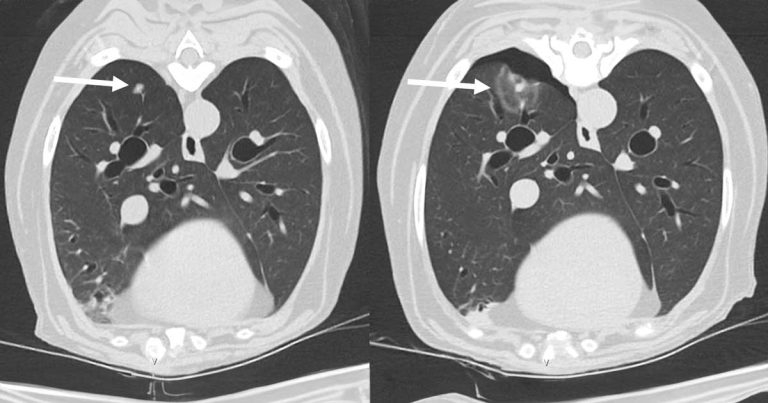

The 7mm lung nodule on a CT scan before (left) and immediately after (right) microwave ablation showing a sphere of ablated tissue and small pneumothorax.

It developed slowly progressive metastatic disease 18 months later, which was managed with minor surgery to remove lymph nodes and chemotherapy, but a solitary slowly growing 7mm nodule in the right caudal lung appeared resistant to the treatment.

For the treatment, the tip of a special needle a few millimetres wide was inserted into the lung nodule under CT guidance, which was headed to create a sphere of thermal ablation that destroys the target mass.